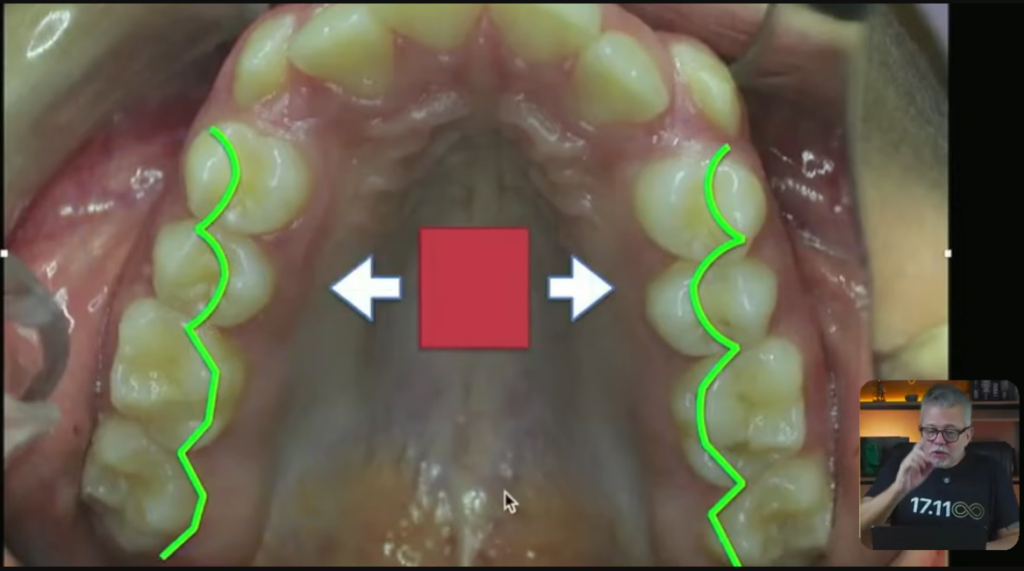

Imagina que é um expansor:

Esse expansor aqui, ele faz uma força nos pré e também nos pré do outro lado:

Então, esse verdinho que você está vendo aqui, ele vai fazer esse tipo de movimento:

Esses pré vão expandir desse jeito que você acabou de ver. Muito mais na região dos pré do que dos molares, tá?

Vai acontecer uma expansão nessa região.

E na ortopedia, a gente também coloca um negócio chamado mola frontal. Ela encosta no lateral e ela leva esse lateralzinho para vestibular:

Eu posso muito bem pegar o diagrama ortodôntico do meu paciente e fazer com que esse diagrama fique mais ou menos com esse formato:

Professor, mas eu posso fazer esse formato de arco no meu paciente que parece um formato de arco um pouco mais quadrado, expansivo, só no fio, assim, só no formato do fio?

Claro que você pode, desde que o corredor bucal da paciente permita um pouco de expansão na região dos prés.

Ah, então quer dizer que aqui eu não precisaria nem de quadriélice, nem de disjuntor, nem de expansor. Eu conseguiria fazer tudo isso com o formato do fio?